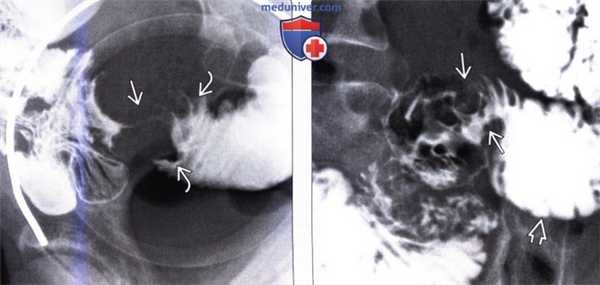

(Слева) На рентгенограмме, полученной во время исследования пассажа бариевой взвеси по тонкой кишке, определяется стриктура терминальных отделов подвздошной кишки в виде «огрызка яблока» с сужением просвета, деструкцией слизистой оболочки и подрытыми краями. Эти изменения являются классическими признаками первичного рака тонкой кишки.

(Справа) На рентгенограмме, выполненной во время исследования пассажа контраста по тонкой кишке, визуализируется объемное образование В тощей кишки с наличием характерных признаков первичного рака тонкой кишки: узловидно утолщенных складок, деструкции слизистой оболочки и сужения просвета. Определяется дилатация отделов кишечника, расположенных выше уровня опухоли.

1. Рентгенография при метастазе в стенку тонкой кишки и лимфоме тонкой кишки:

• Метастазы в стенке тонкой кишки

• Рентгеноскопические исследования с бариевым контрастом (верхних отделов ЖКТ, исследование пассажа бариевой взвеси по тонкой кишке, бариевая клизма):

о Исследованием тонкой кишки, позволяющим выявить как можно больше деталей, является энтероклизма (осуществляемая путем введения трубки в тонкую кишку с последующим растяжением ее просвета)

о Позволяет получить наиболее детализированную информацию о поражении слизистой оболочки и интрамуральном распространении опухоли:

- Не столь применима в случае опухоли, растущей наружу, вне просвета

• Метастазы злокачественной меланомы в тонкой кишке:

о Единичное образование или множественные дискретные подслизистые образования

о Поражения в виде «бычьего глаза» или «мишени» с наличием центральной язвы

• Метастазы рака легкого и молочной железы:

о Являются скиррозными опухолями, имеют тенденцию к обструкции просвета